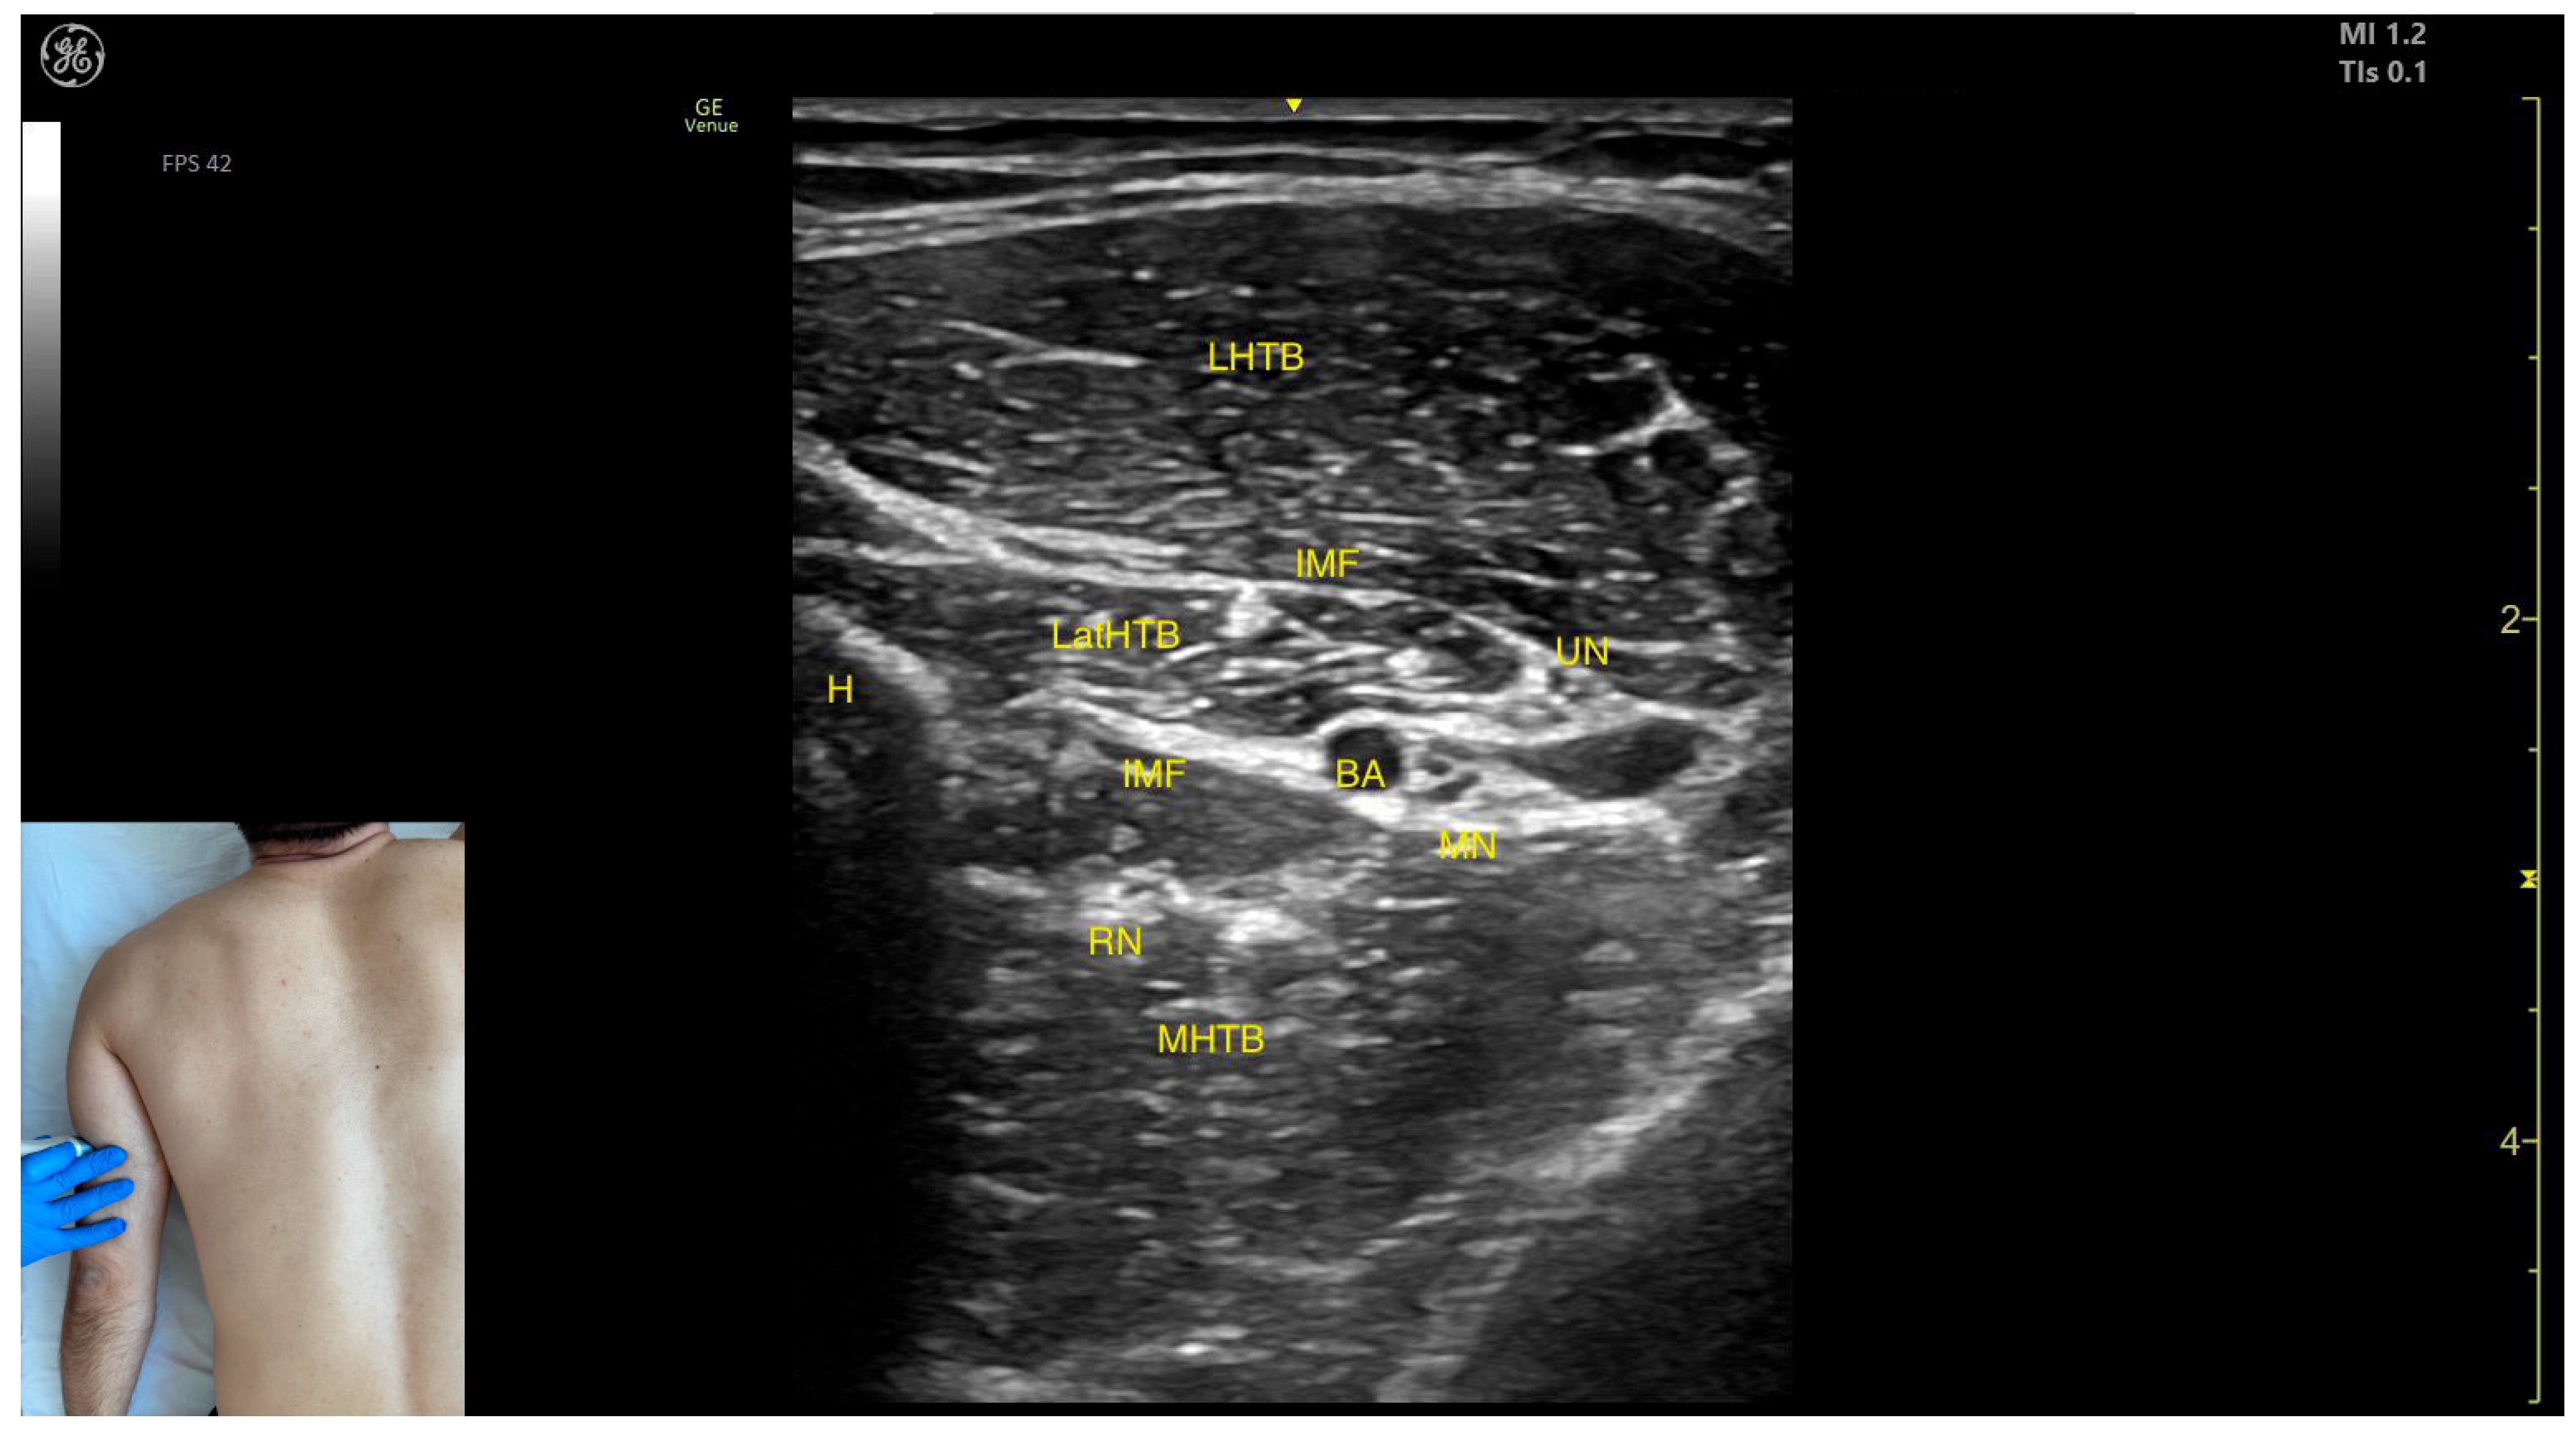

2.7.3. Key Ultrasound Landmarks

- Muscle position: At this level, it represents the only muscle mass in the posterior compartment of the arm.

- Muscle morphology: The TB has three heads—long, medial, and lateral—each of which can be approached individually. These three heads are separated by intramuscular fasciae:- 1.

- Long head (LHTB): Located superficial to the cortical bone of the humerus.

- 2.

- Medial head (MHTB): Found medial to the humeral cortex.

- 3.

- Lateral head (LatHTB): Situated between the long and medial heads.

- Innervation and vascular supply: In the medial portion of the TB, the neurovascular bundle is observed, consisting of three nerves—median, radial, and ulnar—and two vascular structures, namely the brachial artery with its branches and the brachial vein.

- External fascia: The TB features a pronounced fascia that separates it from the superficial plane during BoNT-A injections.

- Dynamic evaluation: During dynamic evaluation, scanning distally toward the elbow joint reveals a decrease in the size of the long and lateral heads, while the medial head shows an increase in size. Muscle contraction is visible during elbow extension maneuvers, confirming its role in this movement [12,50].

2.7.4. Clinical Implications and Injection Strategy

- Long head: Injected at two sites—one at the midpoint of the posterior arm and another 2 cm proximal to this level, closer to the shoulder joint.

- Lateral head: Injected at the midpoint of the posterior arm.

- Medial head: Injected 1 cm distal to the midpoint of the posterior arm.